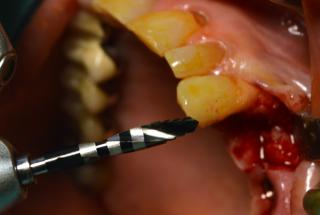

Clinical cases

MPI closely monitors clinical cases in the market to ensure their correct functioning and successful outcome.